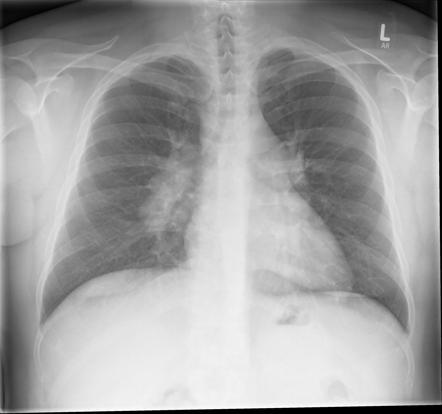

Stages of sarcoidosis on CXR

Stage 0 is a normal chest X-ray

Stage 1 is bilateral hilar lymphadenopathy

Stage 2 is bilateral hilar lymphadenopathy with pulmonary infiltrates

Stage 3 is diffuse pulmonary infiltrates

Stage 4 is pulmonary fibrosis.